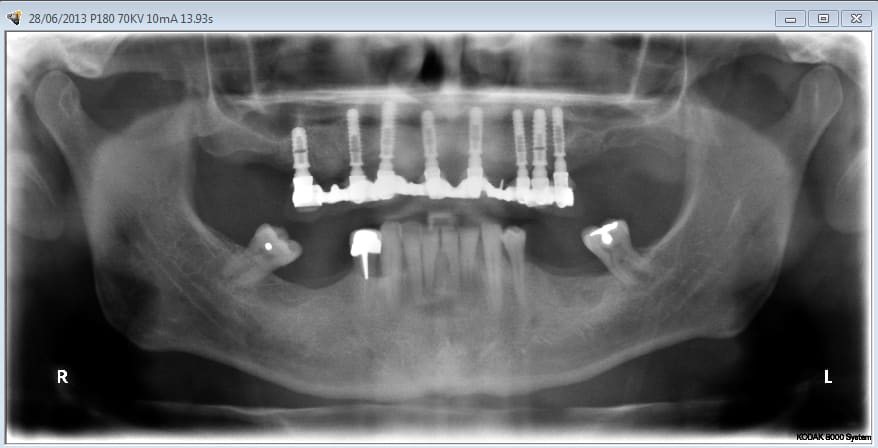

La vidéo présente à partir des plans de traitements, des chirurgies de beotien , des dispositifs médicaux sur mesure positdental et positguide la mise en charge immédiate post-extractionnelle d’un bridge provisoire à armature métal en prothèse fixe sur implants cône morse donc sans vis de maintien. Une question est émise « comment obtient-on ce résultat ? ». Une partie des réponses comme la prédictibilité, la reproductibilité peuvent y être déduite pour d’autre il faudra la bonté de beotien de faire partager les résultats clinique.il nous fait la générosité de poster la phase cicatriciel à 7 jours et des photos de la chirurgie sur un cas.

Vous regardez un cas de mci et ne voyez que l’implant sur 9 (je ne parle pas des derniers qui n’ont que quelques jours) qui posé il y a 4 ans lors d’un sinus lift latéral ne va pas bien, et de 2 (8) qu’un 3ème année pourrait enlever.

Aujourd’hui le protocole serait scanner, discussion avec mes associés paro et ortho, et probablement exo, Mci sans sinus lift.

planif cas 1

Si tu as suivi les cas présentés depuis plusieurs années les bridges provisoires ont une armature métal pour la rigidité du fixateur externe, l’intervention se déroule en 1 seul temps chirurgical donc sans prise d’empreinte, c’est pour cela que je parle de MCI. Pour la passivité du bridge avec le système Nobel Guide et leurs piliers expansifs je n’ai vue aucun cas clinique présenté sur le forum. As-tu déjà utilisé le procédé ? Dans les cas présentés sur la vidéo, aucune clé de positionnement n’a été utilisée, le placement des piliers se fait selon la simulation implantaire assistée par ordinateur, leurs présentations a été faite en prospective par OTP, modèle 3D et à la demande de beotien la solution pilier fixe a été retenu à la place du bridge transvisé. Quel sont les compléments d’information que tu as besoin et ou la photo ne te suffi pas ? Pour le protocole d’une MCI, empreintes des maxillaires, dimension verticale de l’occlusion, définition de l’esthétique souhaitée, prescriptions, réalisation du Positscan, traitement des informations à partir des données DICOM, simulation implantaire assistée par ordinateur, validation, réception des DMSM selon les types d’implants et encastillages les procédures varient. Quel système implantaire utilise-tu ?